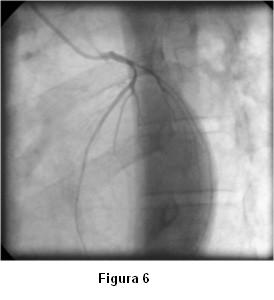

Antes de la finalización del estudio de la coronaria izquierda reitera espasmo (figura 6) que mejora sin necesidad de administración de vasodilatadores (figuras 7 y 8).